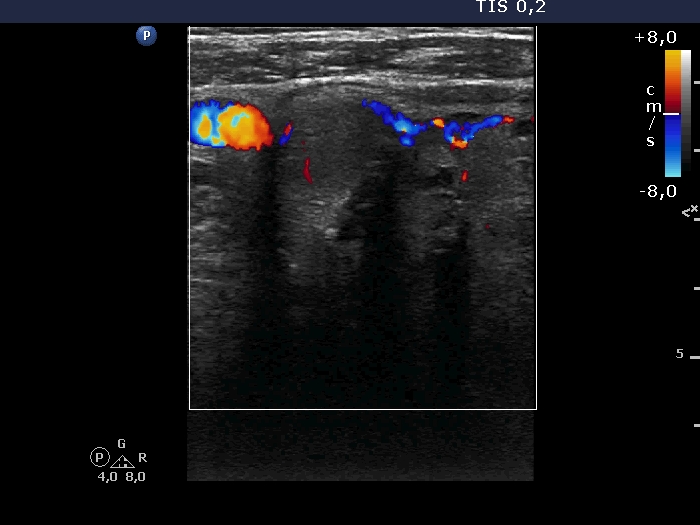

Ultrasonography. A large hypoechoic nodule occupied almost the entire right lobe. The lesion had both microcalcifications and coarse calcifications. The dimensions of the lobe were 58x55xminimum 80 mm, width, depth, length, respectively. The lower pole of the lobe did not come into sight while the patient swallowed. The nodule showed signs of perinodular blood flow. There was a hypoechoic nodule in the left lobe.